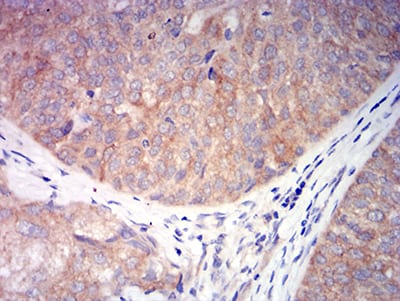

Immunohistochemical analysis of paraffin-embedded human bladder cancer tissues using CHRNA6 mouse mAb with DAB staining.